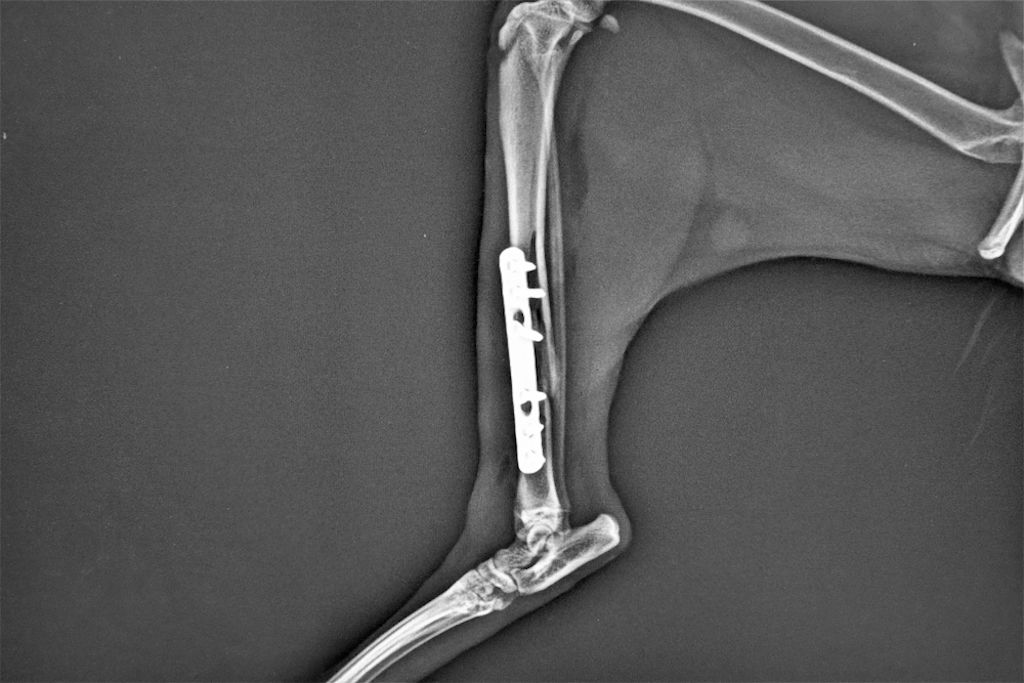

Inserción de placas o clavos

En la cirugía más común para fracturas graves, se utilizan placas metálicas o clavos que se insertan en el hueso fracturado para mantener su posición correcta.

Esta opción es adecuada cuando hay una fractura múltiple o cuando el hueso no puede curarse por sí solo debido a la gravedad de la rotura.